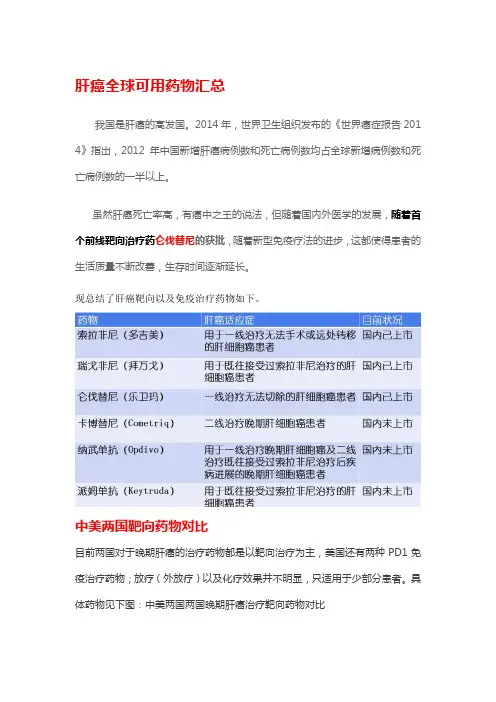

肝癌全球可用药物汇总我国是肝癌的高发国。

2014年,世界卫生组织发布的《世界癌症报告201 4》指出,2012年中国新增肝癌病例数和死亡病例数均占全球新增病例数和死亡病例数的一半以上。

虽然肝癌死亡率高,有癌中之王的说法,但随着国内外医学的发展,随着首个前线靶向治疗药仑伐替尼的获批,随着新型免疫疗法的进步,这都使得患者的生活质量不断改善,生存时间逐渐延长。

现总结了肝癌靶向以及免疫治疗药物如下。

中美两国靶向药物对比目前两国对于晚期肝癌的治疗药物都是以靶向治疗为主,美国还有两种PD1免疫治疗药物;放疗(外放疗)以及化疗效果并不明显,只适用于少部分患者。

具体药物见下图:中美两国两国晚期肝癌治疗靶向药物对比肝癌靶向治疗机制肝癌靶向治疗的基础主要包括信号传导途径和新生血管两方面。

一方面,多激酶抑制剂可以通过抑制血管内皮生长因子受体(VEGFR)、血小板衍生生长因子受体(PDGFR)等阻断肿瘤血管生长;另一方面,又可通过阻断Raf/MEK /ERK等信号传导通路抑制肿瘤细胞增殖。

肝癌双重靶向抗肿瘤作用靶向治疗药物(具体介绍下文)仑伐替尼(乐卫玛®):靶点PDGFR-α、VEGFR1/2/3、FGFR1/2/3/4、K IT、RET。

2018年9月中国获批上市,目前还没有纳入医保。

仑伐替尼单药在中国用于治疗既往未接受过全身系统治疗的不可切除的肝癌患者,是十年来第一个在中国被批准作为肝细胞癌一线系统治疗的新治疗方案,中位总生存期:13. 6个月;中位无进展生存期:7.3个月;客观缓解率:41%。

瑞戈非尼(拜万戈®):靶点PDGFR-α/β、VEGFR1/2/3、KIT、FGFR1/2、RET、B/C-Raf。

2017年3月中国获批上市,目前已纳入国家乙类医保目录。

瑞戈非尼用于既往使用过索拉非尼(多吉美)治疗的肝细胞癌(HCC),成为肝癌HCC二线治疗药物,这也是中国首个肝癌二线靶向药。

瑞戈非尼用于既往使用过索拉非尼的肝细胞癌,中位总生存期:10.6个月;中位无进展生存期:3.1-3. 4个月;总缓解率:7%-11%。